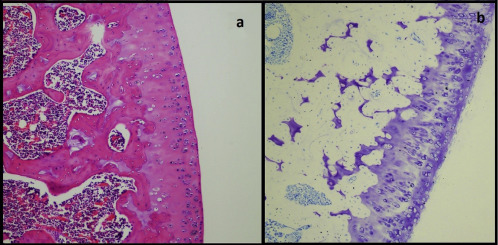

Fig. 2

Fig. 2.

(a) Characteristics of a normal articular structure: intact surface layer, normal morphology and distribution of chondrocytes and a continuous matrix within them. (b) Proteoglycan matrix showing diffuse staining with accentuation in perichondrial areas (Toluidine blue).

Statistically significant differences were found between the control group (11 left knees) and papain-injected group (11 right knees) regarding total Mankin scores (control: 3.91, papain: 14.0; p < 0.001) (Table 1 ). Representative histological lesions in the cartilage of OA-induced rats were; moderate and severe surface irregularities, cleft formation in the transitional and radial zone, hypercellularity and disrupted columns of chondrocytes and multilayered tidemark. On the 63rd day, lesions were not reduced and got worse in Group 1. Representative histological lesions in Group 1 were; loss of severe matrix loss, moderate pannus formation, all of the above and large patches of cell death and sloughing of layers till mid-zone (Fig. 2  ;  Fig. 3 ). On the 63rd day, there was a statistically significant difference between Group 1 and Group 2, between Group 1 and Group 3 regarding total Mankin scores (Group 1: 20.27, Group 2: 10.2, Group 3: 7.18) (Fig. 4  ;  Fig. 5 ). Group 3 showed statistically significant improvement in terms of the proteoglycan content of matrix when compared to Group 2 (p < 0.05). Descriptive histological lesions with scores are presented in Table 2  ;  Table 3 .